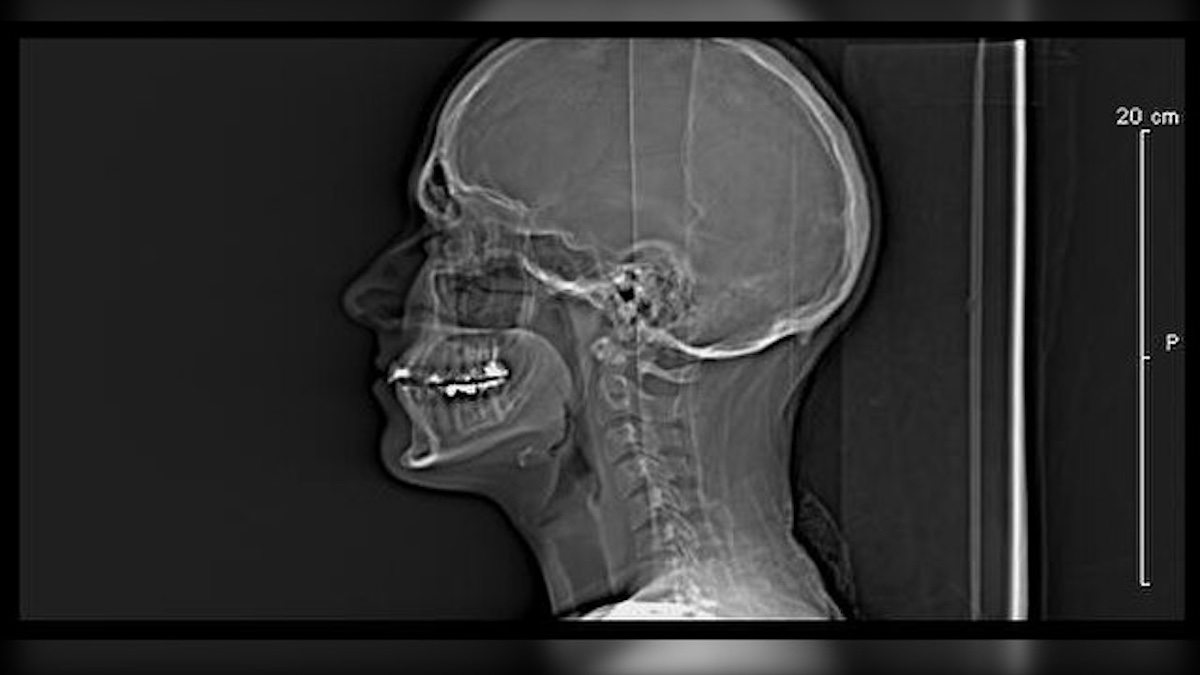

The anesthesiologist, Dr. Anthony Gyamfi, was performing a standard procedure meant to ease pressure around East’s brain before his cancer surgery. East was scheduled to have his right eye and surrounding bone removed to treat cancer, but what followed became one of Florida’s most notorious cases of medical malpractice.

According to The Washington Post, the surgical team had drawn 50 cubic centimeters of cerebrospinal fluid (CSF) before the procedure. That fluid was supposed to be reinjected later. However, in a tragic mix-up, Dr. Gyamfi instead picked up a syringe containing glutaraldehyde — a toxic chemical preservative used to disinfect or preserve tissue — and injected it into East’s spinal canal, instead.